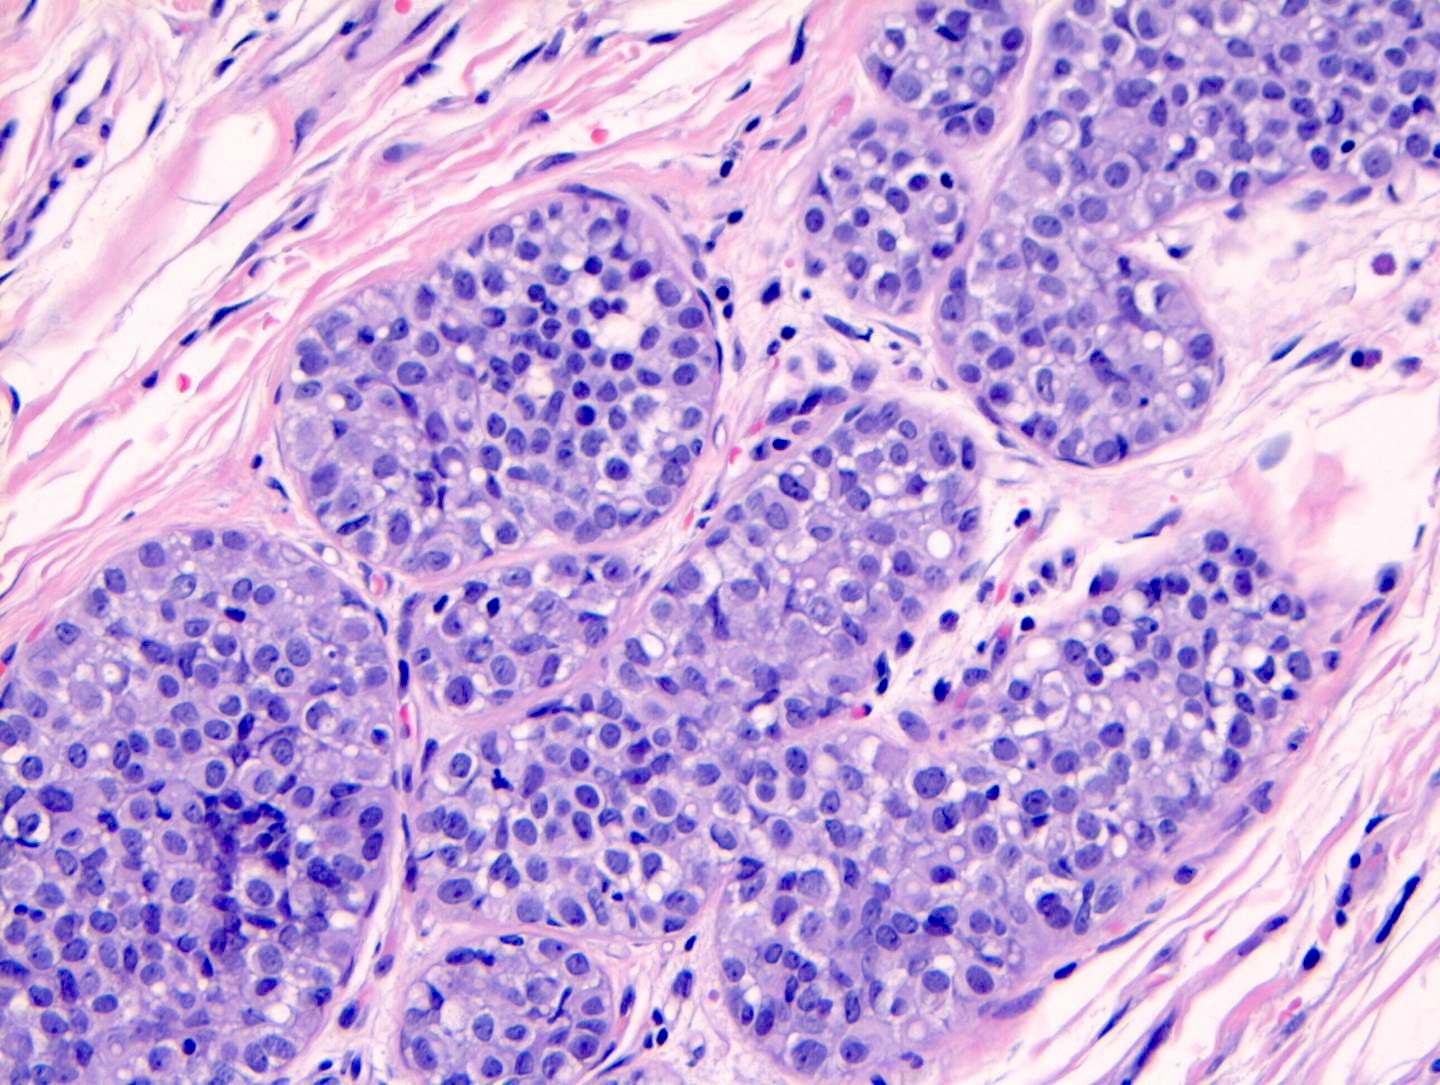

Microscopic (histologic) description

- LCIS involves the terminal duct lobular unit (TDLU), filling and distending acini

- > 50% of the acini in a TDLU must be filled and expanded to qualify as LCIS; otherwise, called atypical lobular neoplasia

- Lobular distention is defined as the presence of ≥ 8 cells in the cross sectional diameter of an acinus

- Involved lobules may be compared with uninvolved lobules to estimate the degree of distension

- Classic LCIS cells are monomorphic, evenly spaced, loosely cohesive and do not show polarization or gland formation

- 2 types of cells are described:

- Type A: nuclei are small to slightly enlarged (1 - 1.5x size of lymphocyte) with uniform round nuclei and inconspicuous nucleoli

- Type B: nuclei larger (2x size of lymphocyte), more abundant cytoplasm and more prominent nucleoli

- Type A and B cells can coexist in the same lesion

- Cytoplasm of LCIS cells is typically pale to lightly eosinophilic with indistinct cell borders

- In almost all cases of LCIS, at least some cells contain intracytoplasmic vacuoles or lumina, which may contain an eosinophilic globule; this feature is not specific to LCIS

- Vacuoles may be subtle such that special histochemical stains for mucin are required in order to demonstrate; alternatively, they may be large enough to push the nucleus against the cell membrane and produce signet ring cell forms

- Outer layer of myoepithelial cells is retained in the acini and ducts involved but it may be attenuated

- Classic LCIS does not show significant nuclear pleomorphism or mitosis

- Classic LCIS may rarely display single cell apoptosis or minute foci of necrosis but typically does not show comedo type necrosis

Microscopic (histologic) images

Contributed by Anna Biernacka, M.D., Ph.D.